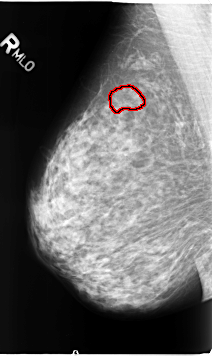

B_3133_1.RIGHT_MLO

RIGHT_MLO LINES 4624 PIXELS_PER_LINE 2752 BITS_PER_PIXEL 12 RESOLUTION 50 OVERLAY

FILE: B_3133_1.RIGHT_MLO.OVERLAY

TOTAL_ABNORMALITIES 1

ABNORMALITY 1

LESION_TYPE CALCIFICATION TYPE PLEOMORPHIC DISTRIBUTION CLUSTERED

ASSESSMENT 4

SUBTLETY 2

PATHOLOGY BENIGN

TOTAL_OUTLINES 1

BOUNDARY